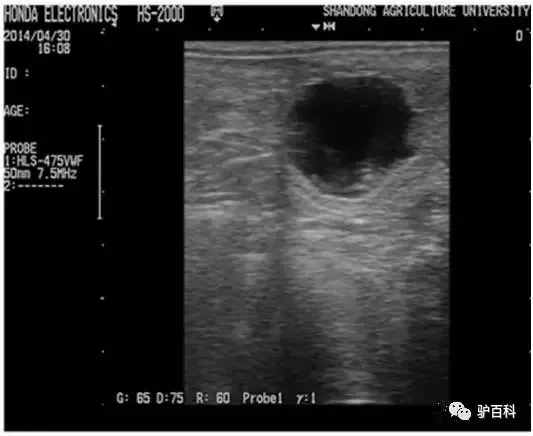

B超检查主要是通过B超图像查看子宫内是否有胚泡来断定妊娠情况。妊娠后12天用B超即可看到子宫内胚泡的情况,因此B超检查适合做早期孕检。

驴妊娠后,在子宫角内会有胚泡的出现,胚泡中含有大量的液体,因此屏幕上就会出现一个黑色的图像,此即为胚泡。